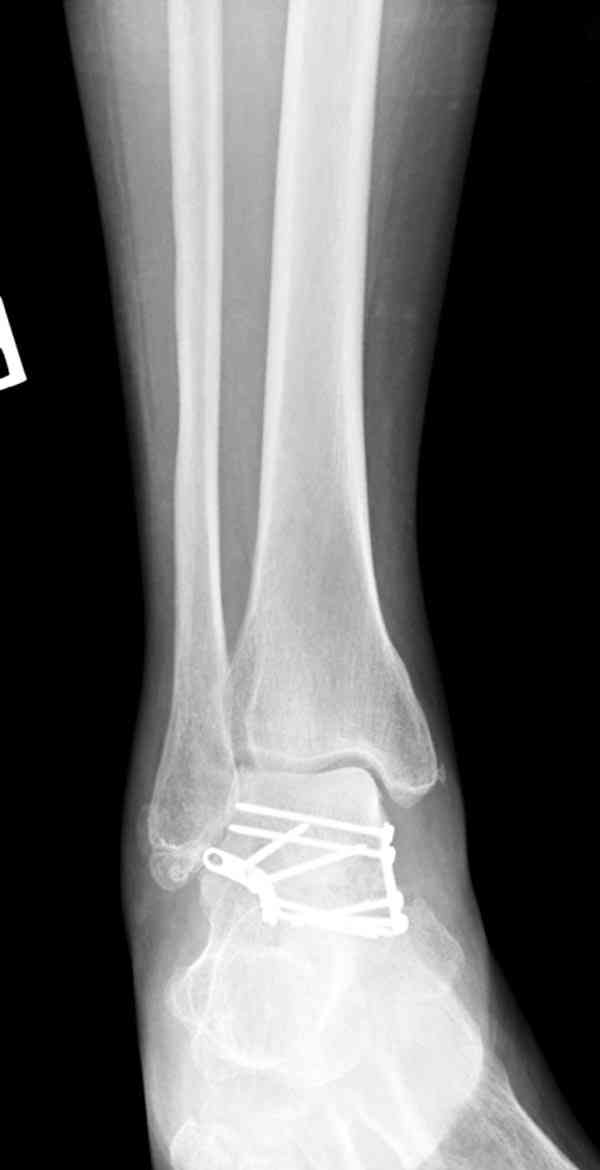

Случай с множественным оскольчатым переломом тарана оперированный из двойного доступа.

Через 8 мес.: